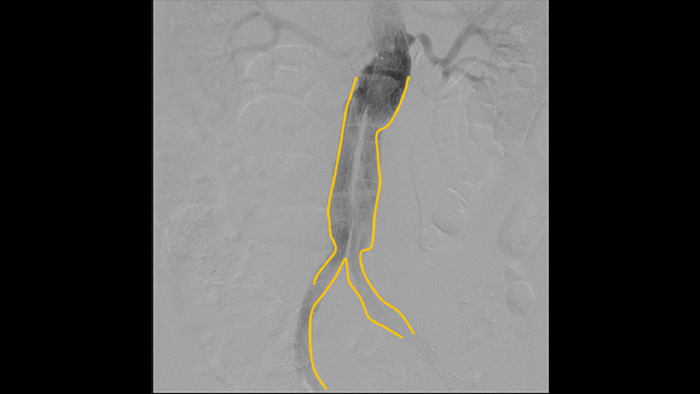

L’outil de contour permet de marquer facilement une bifurcation ou des branches latérales en dessinant simplement sur le moniteur du poste de visualisation mobile avec votre doigt ou une souris connectée en externe.

À l’aide de l’arceau mobile Philips Zenition, le docteur Vila obtient des images de haute qualité qui lui permettent d’effectuer la plupart des procédures vasculaires à faible dose.

Grâce au système Zenition, la qualité des images en angiographie par soustraction numérique s’est considérablement améliorée. Nous ne voyons plus d’image granuleuse. Nous voyons une image très claire."

L’angiographie par soustraction numérique (ASN) est utilisée dans les procédures vasculaires interventionnelles pour visualiser clairement les vaisseaux sanguins en retirant les structures qui peuvent masquer la visibilité des vaisseaux. Le guidage fluoroscopique superpose une image de contraste soustraite acquise précédemment sur la fluoroscopie en temps réel, ce qui vous permet de suivre un appareil sans réinjecter de produit de contraste.